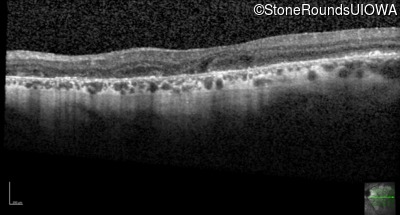

Age at visit: 55 years

Age at visit: 56 years

Age at visit: 57 years

Age at visit: 57 years (Visit 2)

Age at visit: 57 years (Visit 3)

Age at visit: 57 years (Visit 4)

Age at visit: 58 years

Age at visit: 58 years (Visit 2)

Age at visit: 59 years

Age at visit: 59 years (Visit 2)

Age at visit: 60 years

Age at visit: 60 years (Visit 2)

Age at visit: 61 years

Age at visit: 62 years

Age at visit: 62 years (Visit 2)

Age at visit: 63 years

Age at visit: 63 years (Visit 2)

Age at visit: 65 years

Age at visit: 66 years

Age at visit: 67 years